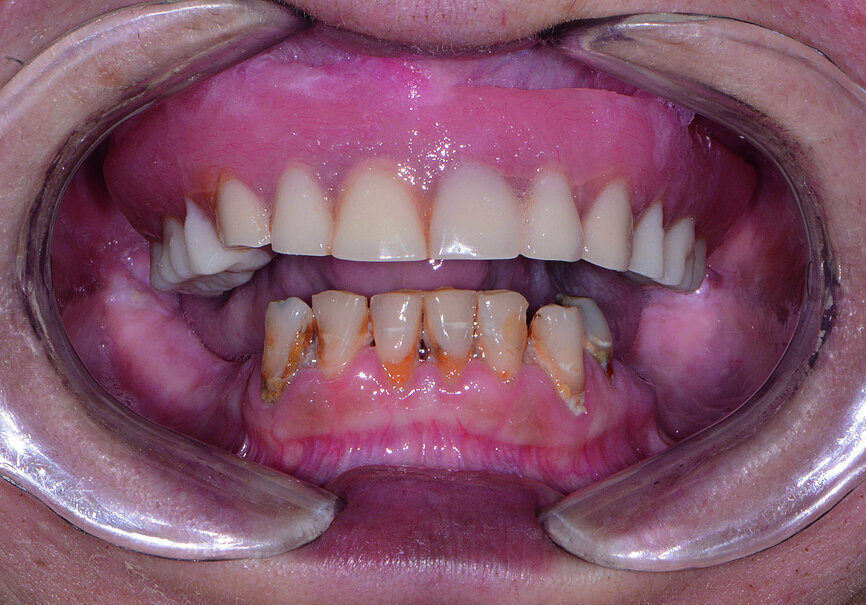

Fig. 1: Pre-op retracted view.

Fig. 2: Pre-op retracted view without denture.

A female patient in her mid-fifties presented for treatment with an edentulous maxilla and grossly decayed, hyper-erupted mandibular dentition (Figs. 1 & 2). The patient was a heavy smoker, had not seen a dentist in several years, and was not taking proper care of her remaining teeth owing to pain and discomfort. The patient’s maxillary denture had become increasingly loose-fitting since losing her teeth nearly a decade prior. Her desire for a restoration that felt and functioned more like natural teeth led her to my practice, where she could undergo the surgical and prosthetic phases of treatment under one roof. Intra-oral and radiographic evaluation indicated sufficient bone volume for full-arch implant therapy.